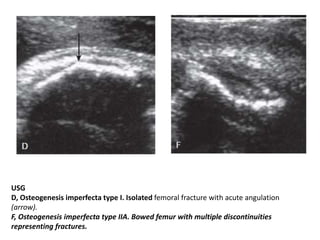

Prenatal ultrasonography: Most useful in

evaluating OI types II and III by 2nd trimester.

Findings include bowing, shortening and

angulation of the long bones due to fractures

and easy visualization of intracranial

structures due to decreased ossification of the

skull vault.

3 important US criteria of specific diagnosis of

OI-type-II:

• a) FL greater than 3SD below the mean,

• b)Demineralization of calvarium,

• c) Multiple fracture within a single bone.

USG

D, Osteogenesis imperfecta type I. Isolated femoral fracture with acute angulation

(arrow).

F, Osteogenesis imperfecta type IIA. Bowed femur with multiple discontinuities

representing fractures.

Osteogenesis Imperfecta Diagnosis 30 Prenatalultrasonography: Most useful in evaluating OI types II and III by 2nd trimester. Findings include bowing, shortening and angulation of the long bones due to fractures and easy visualization of intracranial structures due to decreased ossification of the skull vault. 3 important US criteria of specific diagnosis of OI-type-II: • a) FL greater than 3SD below the mean, • b)Demineralization of calvarium, • c) Multiple fracture within a single bone.

• 31.

USG D, Osteogenesis imperfectatype I. Isolated femoral fracture with acute angulation (arrow). F, Osteogenesis imperfecta type IIA. Bowed femur with multiple discontinuities representing fractures.